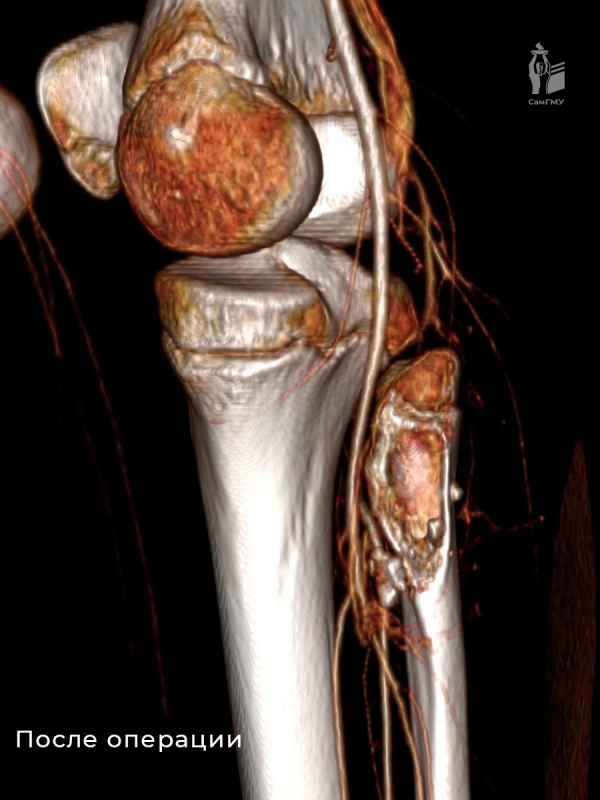

Сложность операции заключалась в необходимости сохранения всех функционально важных элементов. Для выполнения этой трудоёмкой задачи была сформирована мультидисциплинарная команда, которая включала детского сосудистого хирурга Николая Свечкова из Самарского областного клинического кардиологического диспансера. После проведения тщательной диагностики, включая КТ-ангиографию, врачи провели оперативное удаление нароста. Хирурги аккуратно отделили образование от малоберцовой кости и мягких тканей, освободив подколенную артерию без нанесения повреждений.

На данный момент пациент проходит курс реабилитации. Специалисты оптимистично смотрят на перспективы его восстановления и уверены, что уже этой осенью юный спортсмен сможет вернуться к полноценным тренировкам.